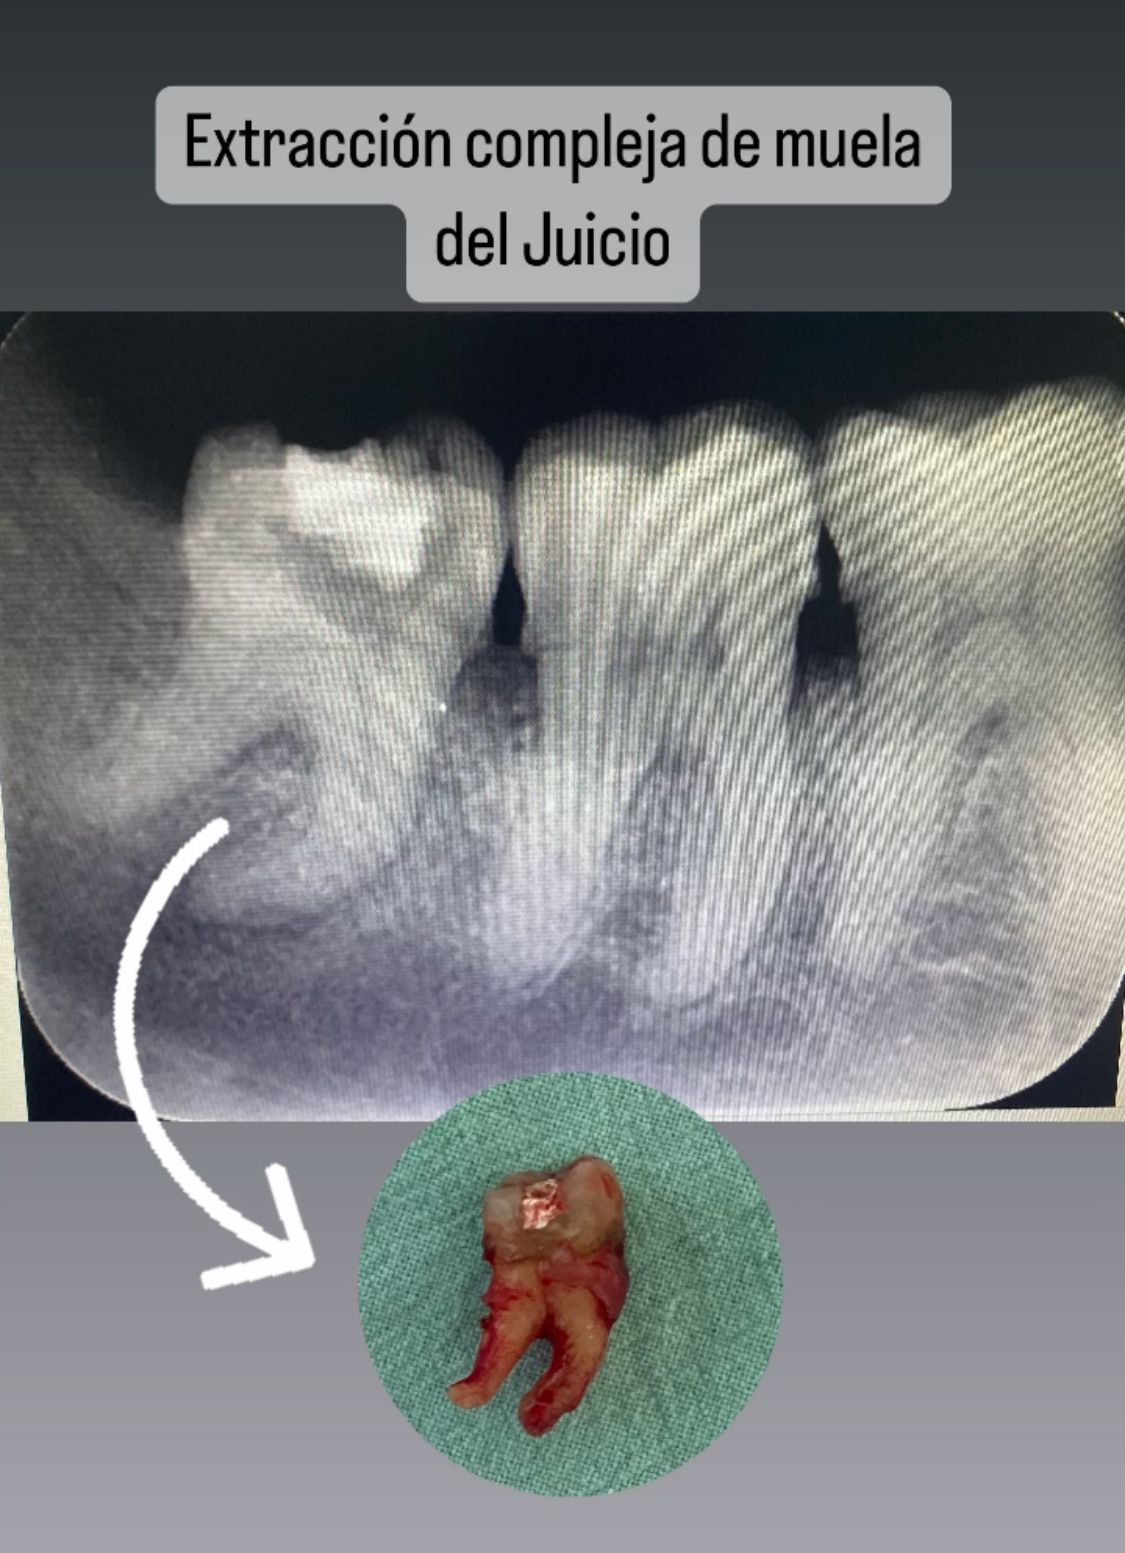

• Clínica Odontológica Cenit Sucursal Hochstetter Cirugia compleja  •